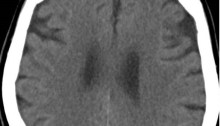

Diagnosis and Management of Transient Ischemic Attack and Acute Ischemic Stroke A Review JAMA 2021.

Esta revisión resume la evidencia actual con respecto al diagnóstico de ACV isquemico y Accidente Isquemico transitorio , métodos de manejo temprano para mejorar los resultados y prevenir accidentes cerebrovasculares isquémicos recurrentes.